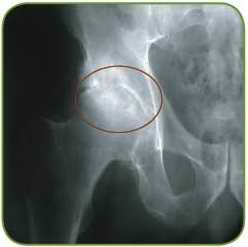

The man is 49 years old. Primary coxarthrosis

The most common cause of joint deformity is primary and secondary arthrosis or degenerative-dystrophic disease of the musculoskeletal system, which is characterized by progressive destruction of the cartilaginous surface of the head and cavity, which leads to a sharp narrowing of the joint gap.

Secondary arthrosis of the hip arises against the background of dysplasia or congenital dislocation of the thigh, aseptic necrosis of the head and femur, Perthes disease, suffered trauma (bruise, fracture, dislocation, microtrauma), inflammatory process (coxitis).

The pain that accompanies the process of destruction of the cartilaginous surface of the joint, already at the initial stages forces you to spare the aching leg and restrict movement in the affected joint, which contributes to the appearance of contractures.